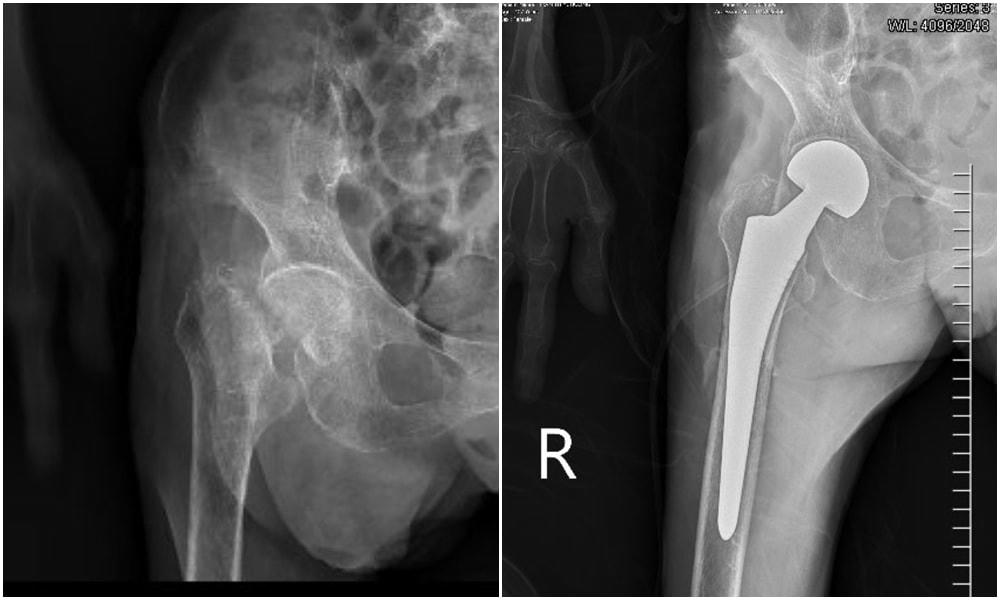

Bệnh nhân là cụ Trần Thị Ch. (107 tuổi) trú tại phường Dương Huy, thành phố Cẩm Phả. Theo gia đình cho biết, cách đây 2 tháng cụ Ch. bị ngã đập mông xuống nền cứng, sau tai nạn hạn chế vận động háng phải. Do thấy cụ tuổi cao sức yếu nên sau khi thăm khám tại y tế cơ sở gia đình quyết định đưa cụ về nhà chăm sóc theo dõi. Tuy nhiên tình trạng ngày càng nặng nề hơn, đùi phải sưng đau, mất vận động, sinh hoạt phụ thuộc vào con cái. Gia đình đưa cụ đến khám tại Bệnh viện Đa khoa tỉnh, qua thăm khám và chụp x-quang, các bác sĩ chẩn đoán cụ Ch. bị gãy cổ xương đùi phải và được chỉ định mổ thay khớp háng nhân tạo.

Gãy cổ xương đùi là một tai nạn hay gặp ở người cao tuổi, chủ yếu là do ngã trượt chân trên nền cứng, ngã đập vùng hông xuống đất. Phẫu thuật thay khớp háng hiện là phương pháp điều trị tối ưu đối với những ca gãy cổ xương đùi do chấn thương, giúp phục hồi chức năng vận động. Đây là kỹ thuật khó, được triển khai chủ yếu ở các bệnh viện lớn có đội ngũ phẫu thuật viên dày dặn kinh nghiệm cùng các trang thiết bị máy móc hiện đại.